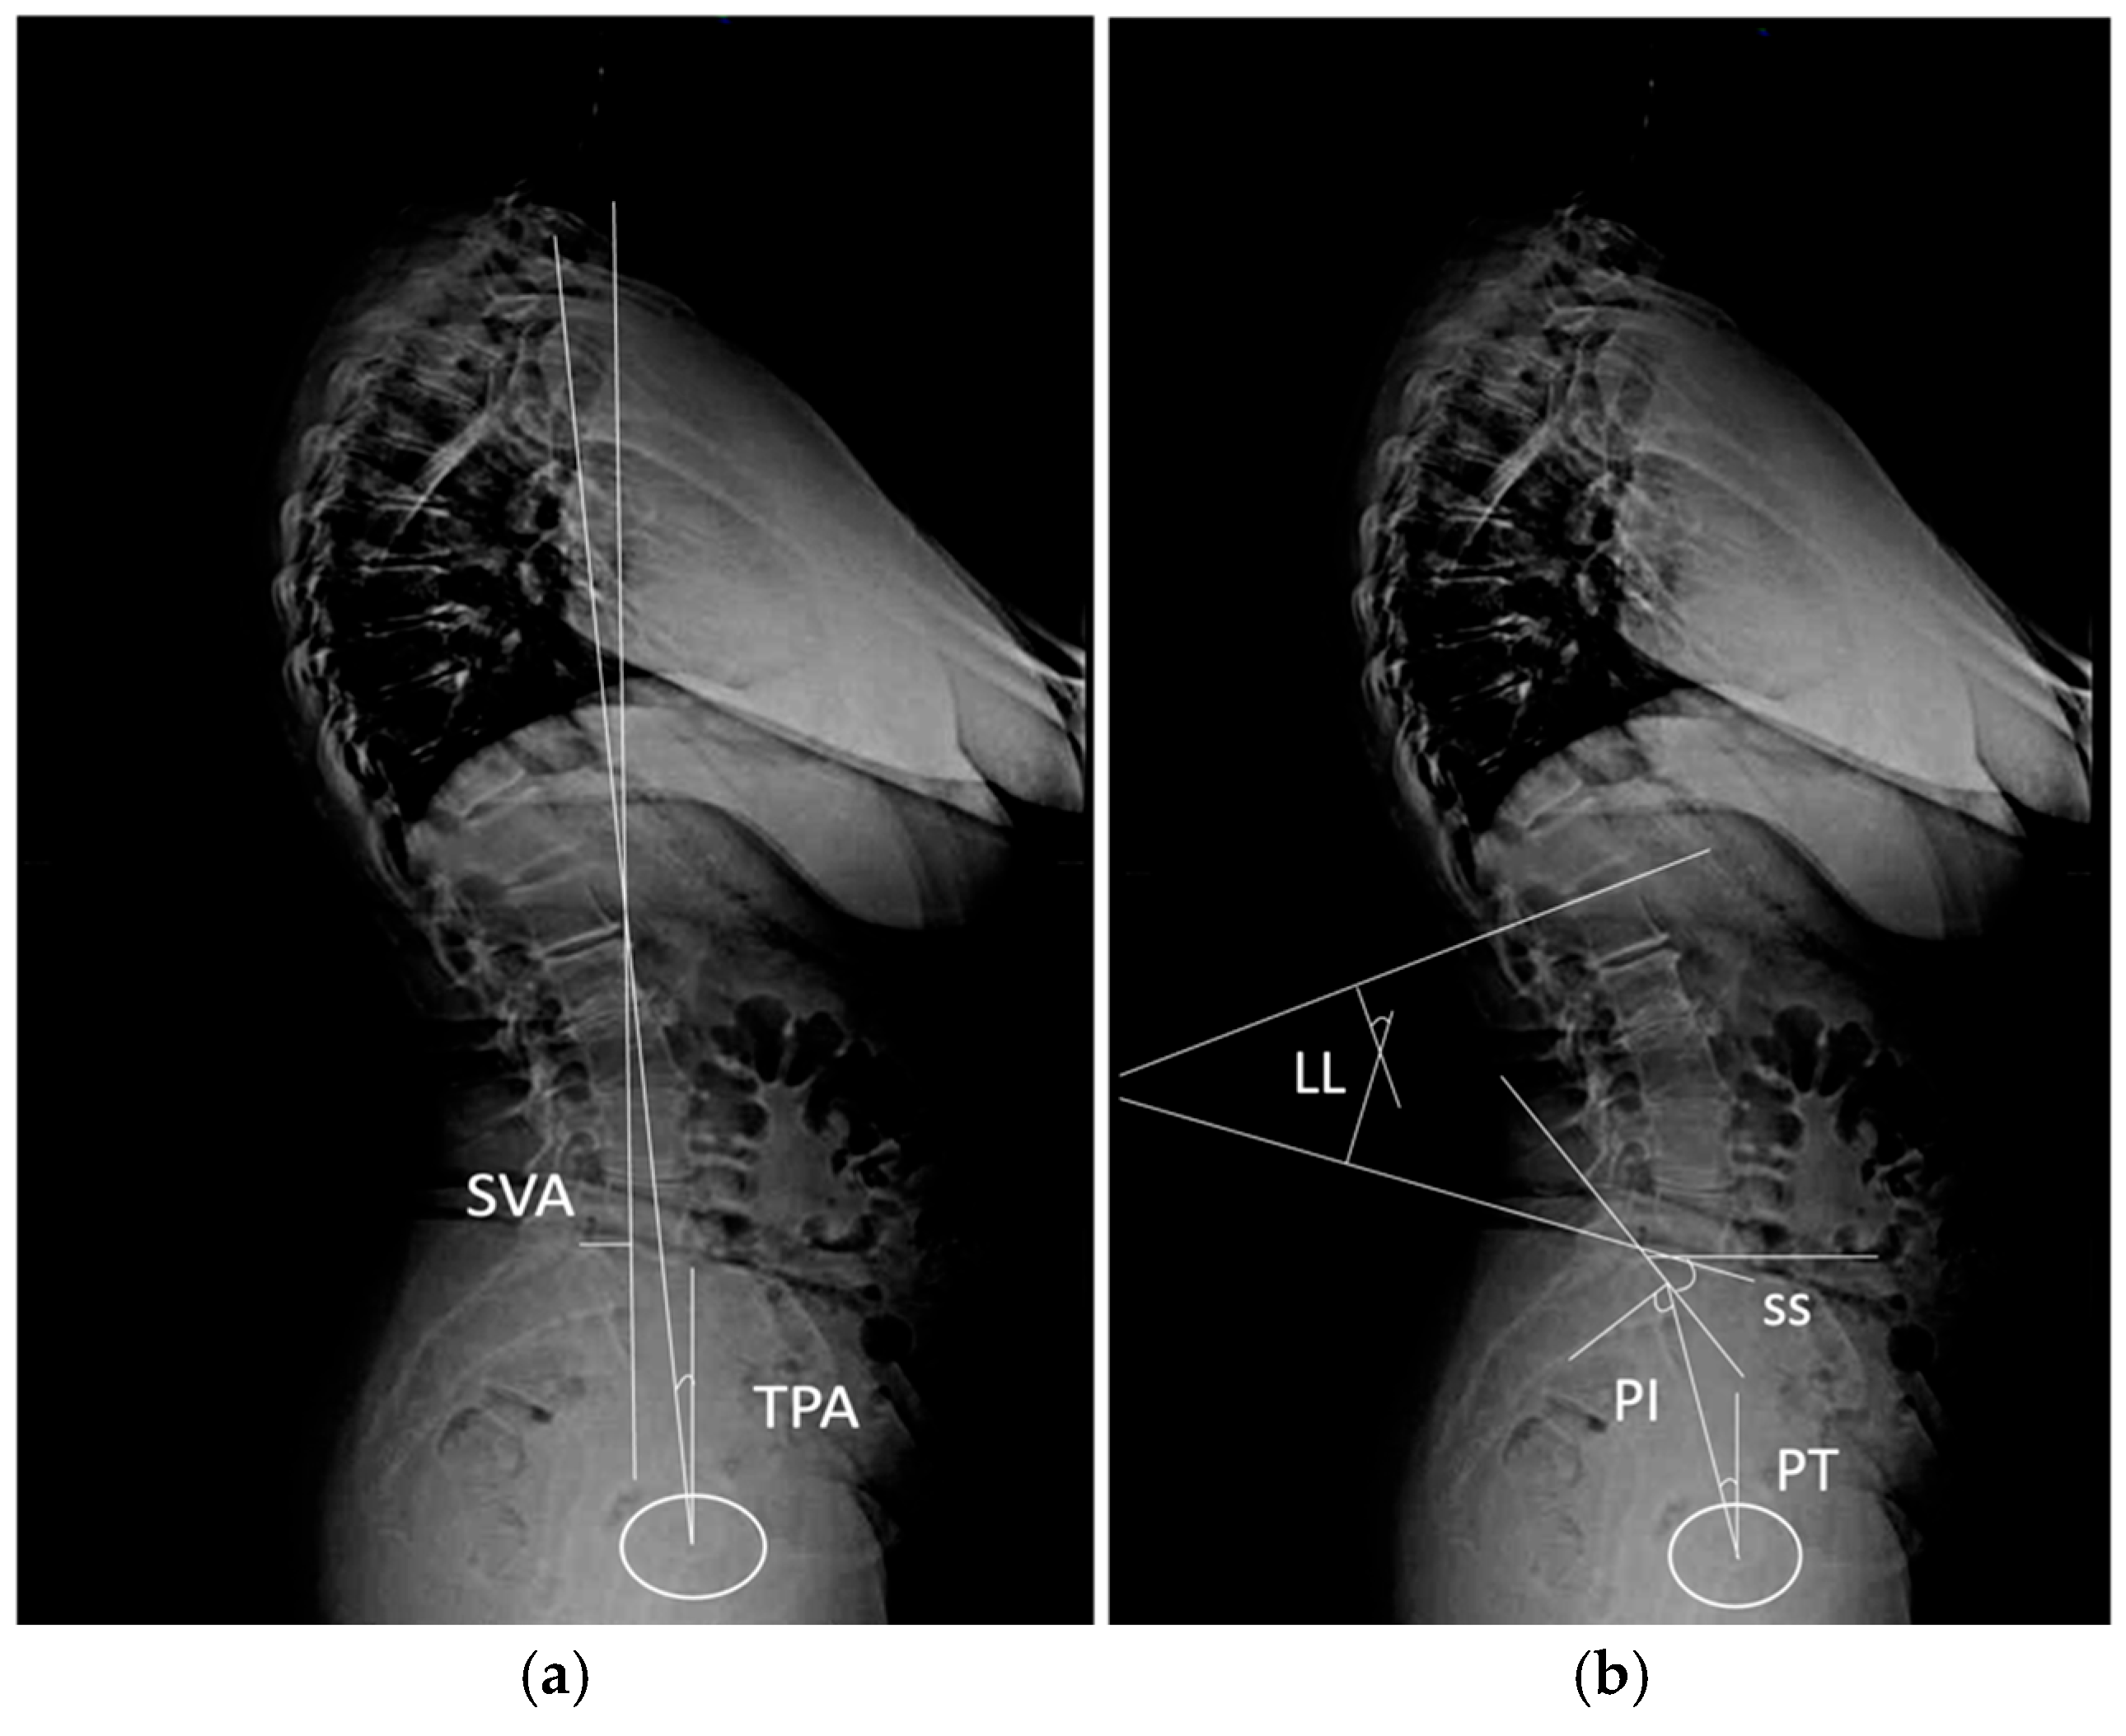

2.2. Imaging Analysis Measurements